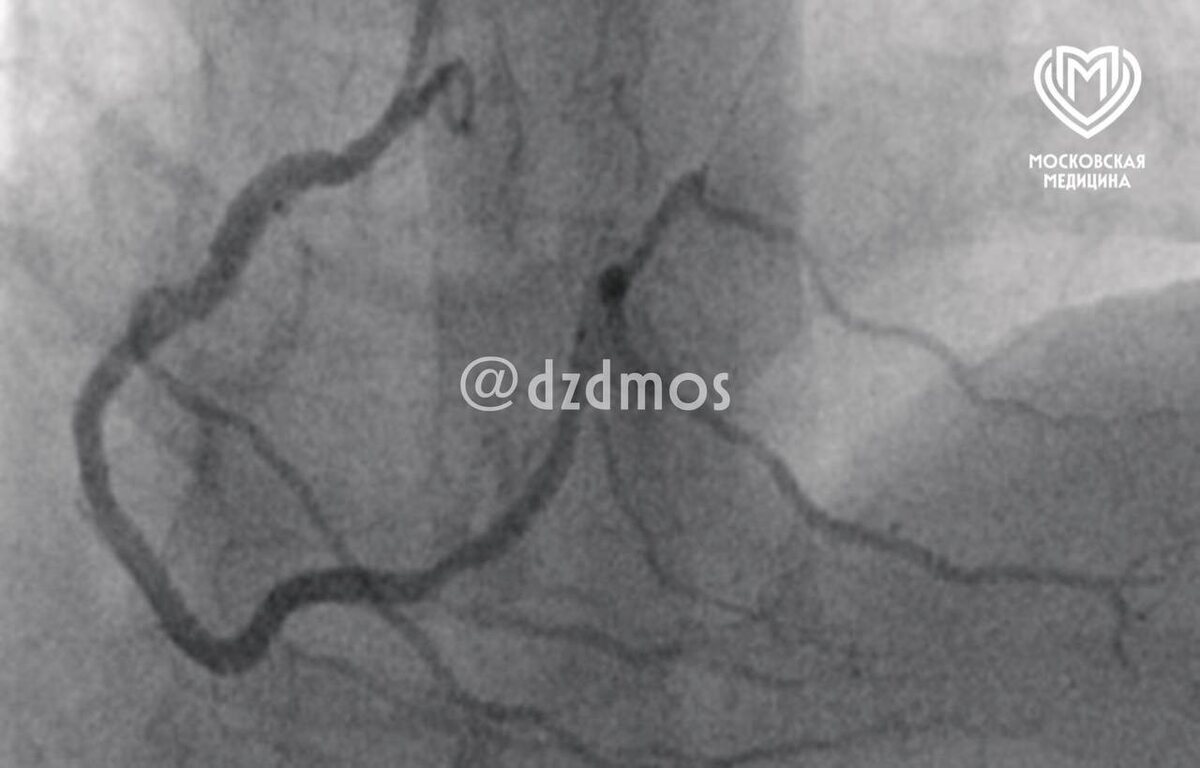

Москвич съел кусок свинины и сразу почувствовал себя плохо, его госпитализировали на скорой в больницу. Врачи обнаружили у него кардиогенный шок. Оказалось, у него случился редкий случай синдрома Коуниса первого типа (острый коронарный синдром вызванный аллергической реакцией). Он встречается крайне редко и требует неотложной помощи.

В больнице состояние мужчины удалось стабилизовать, сейчас он выписан домой и чувствует себя хорошо — сообщают столичные медики.